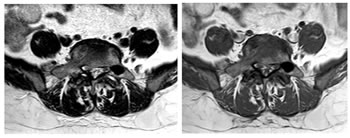

CASE 2

T1 AND T2 W AXIAL IMAGES SHOWING DIFFUSE DISC BULGE WITH SEVERE BILATERAL FACETAL ARTHROPATHY AND LIGAMENTA FLAVA THICKENING AT L5-S1 LEVEL CAUSING MODERATE THECAL SAC STENOSIS, NARROWING OF LATERAL RECESS WITH COMPRESSION OVER BILATERAL TRAVERSING NERVE ROOTS. AN INTRASPINAL SYNOVIAL CYST IS ALSO SEEN ARISING FROM FACET JOINT ON THE RIGHT.